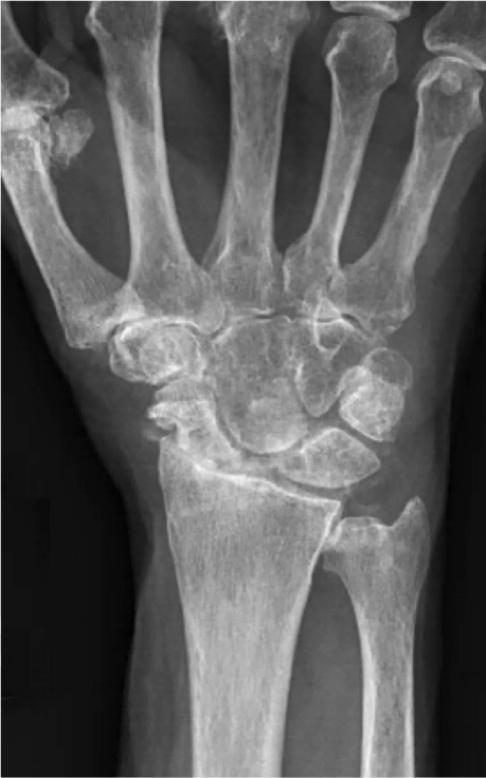

After your hand and wrist has been examined, an X-ray usually determines the degree of damage to the wrist. However, as is often the case, the findings on the X-ray may not correlate with the findings on examination. Some patients may have severe arthritis on their X-ray, yet have very mild symptoms.

X-rays normally show a gap between the bones, as the bones are lined with smooth cartilage, which doesn’t show up on an X-ray. If the cartilage is reduced or absent, the gap between the bones is also reduced, and the ends of bones rub against each other. The body tries to react by making more bone at the edges of the joint. Within the wrist joint, inflammation may develop and this may be painful.